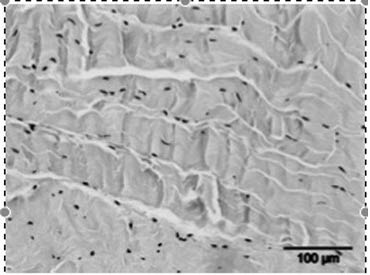

2) Weefselregeneratie

Een tweede hypothese is dat ESWT een positief effect heeft op weefselregeneratie door:

- De toename van neovascularisatie in de pees-bot overgang.

- Het opwekken van groeifactoren zoals vasculo-endothelial growth factor (vegf).

- Het stimuleren van de collageenproductie en het afvoeren van beschadigd collageen, wat resulteert in een verhoogde matrix-turnover.

- Het beïnvloeden van stamcelmigratie en -proliferatie via mechanotransductie.

- De stijging in de celpermeabiliteit. De stimulatie van de celdeling.